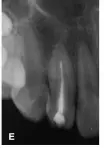

25個(gè)月后復(fù)診:X線片顯示i根尖區(qū)暗影消失,主根管根尖基本閉合,根尖愈合(圖1E)。復(fù)診時(shí)發(fā)現(xiàn)同為牙中牙的2牙體稍變色,牙髓熱測(cè)試無(wú)反應(yīng),診斷為2牙髓壞死,2開(kāi)髓后可探及內(nèi)陷根管的根尖止點(diǎn),測(cè)量工作長(zhǎng)度為22mm,25~30號(hào)擴(kuò)挫后Vitapex充填內(nèi)陷根管,磷酸鋅水門(mén)汀封洞(圖1F),調(diào)牙合消除2咬合干擾,囑以后每隔半年復(fù)診1次,適時(shí)行內(nèi)陷根管的根管治療。

圖1E:治療后25個(gè)月4主根管根尖閉合;F::2 Vitapex充填內(nèi)陷根管